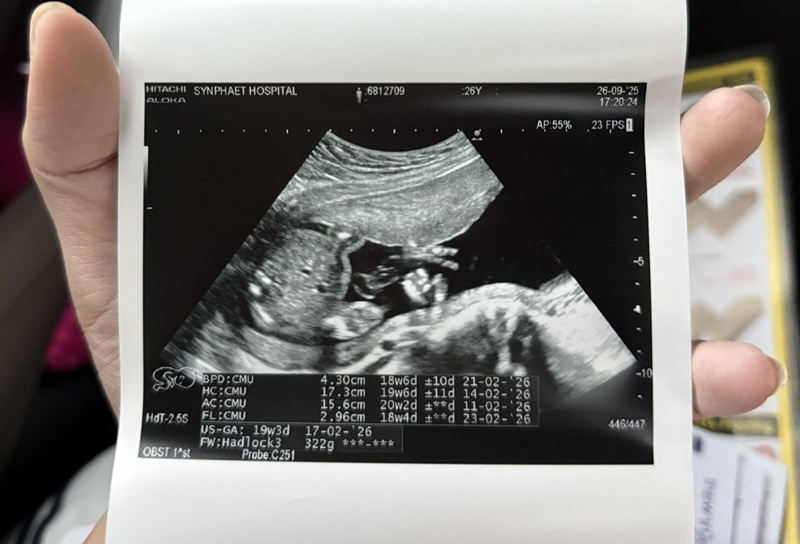

ครูเบียร์ นุติญา อุ้มท้องเข้า รพ. สามี โปรต้า อภิภู เทียนไชย สุดห่วงวอนให้พัก หวั่นกระทบลูกในท้อง เผยสาเหตุเป็นเพราะอะไร หลังนักร้องลูกทุ่งสาว ครูเบียร์ นุติญา เข้าพิธีแต่งงานกับสามีนักกอล์ฟ โปรต้า อภิภู เทียนไชย พร้อมประกาศข่าวดีตั้งท้องลูกคนแรกเมื่อเดือนสิงหาคมที่ผ่านมา ท่ามกลางความยินดีของแฟน ๆ แต่ล่าสุด (29 กันยายน 2568) ก็ทำเอาแฟน ๆ ต่างตกใจไปตาม ๆ กัน หลัง ครูเบียร์ นุติญา ออกมาเผยภาพขณะนั่งรถวีลแชร์เข้ารักษาตัวในโรงพยาบาล และยังจับท้องตัวเองอยู่ด้วยสีหน้ากังวล จนแฟน ๆ ต่างเป็นห่วงและสงสัยว่าเกิดอะไรขึ้น ครูเบียร์ นุติญา ได้เผยอาการป่วยผ่านแคปชั่นว่า "จากเหตุการณ์เมื่อสามวันที่แล้วเบียร์รู้สึกตุบ ๆ ในท้อง รู้สึกแปลก ๆ และได้ถามทุกคนว่าอาการตุบ ๆ อยู่ตรงท้องนี่คืออาการของลูกดิ้นหรือเปล่า เพราะเราไม่เคยท้องมาก่อน ทุกคนบอกว่าน่าจะลูกดิ้น แต่เบียร์ก็รู้สึกผิดปกติอยู่ดี เบียร์เลยได้ไปหาคุณหมอ เนื่องจากตอนนั้นมีอาการปวดหัว ปวดเบ้าตาร่วมด้วย เพราะกินยาพาราก็ไม่หาย วันต่อมาก็เป็นอีกและอาการปวดหน่วงท้องยังมีอยู่ ก็เลยตัดสินใจไปหาคุณหมอที่ฝากครรภ์ แล้วคุณหมอก็ได้อัลตราซาวด์ ได้ผลสรุปว่า "มดลูกบีบตัว" ซึ่งมันไม่ควรที่จะเกิดขึ้นกับคนท้องระยะครรภ์ประมาณ 4-5 เดือน แต่มันควรจะเกิดขึ้นสำหรับคนท้องอายุครรภ์ 7-8 เดือน คุณหมอเลยให้งดให้เดินทางไกล งดยืนนาน ๆ งดการขยับเร็ว และให้ใส่ผ้าพยุงครรภ์ไว้ เนื่องจากกลัวว่าจะมีผลกระทบต่อเบบี๋ในครรภ์ เพราะอาจจะเสี่ยงคลอดก่อนกำหนด แล้วคุณหมอก็ให้ยามาทานแล้วค่ะ แต่อาการยังไม่หาย.." พร้อมกันนี้ ครูเบียร์ นุติญา ยังเผยว่า ยาพาราที่กินนั้นทางคุณหมอสั่งจ่ายให้ ไม่ได้หาซื้อกินเอง ขณะที่คุณสามี โปรต้า ก็เข้ามาคอมเมนต์ด้วยอาการเป็นห่วงว่า "ขอร้องให้พักบ้าง"